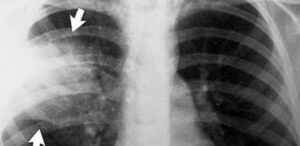

Как выглядит пневмония на снимке

Рентген грудной клетки по-прежнему является золотым стандартом в диагностике большинства респираторных патологий. Пневмония не исключение; признаки патологии обнаружить на рентгеновском снимке несложно. Рентгенологическое исследование важно для постановки точного диагноза, а также играет ключевую роль при дифференциальном обследовании. Важно иметь общее представление о том, как выглядит пневмония у взрослых и детей. Рентген снимок атипичной пневмонии Атипичная …